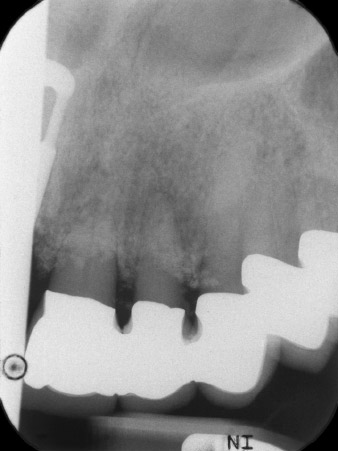

The x-ray revealed horizontal bone loss around teeth 21 and 22 (Fig. 1). When the crown block was removed, these teeth were unintentionally extracted with it.